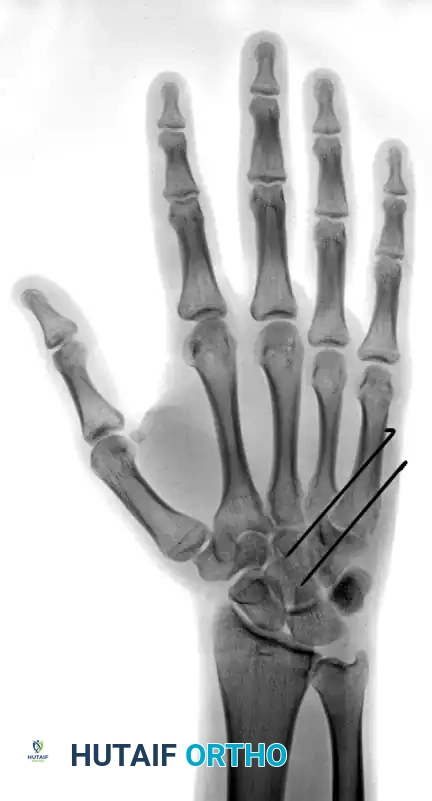

Standard posteroanterior (PA), lateral, and oblique radiographs are mandatory. However, the overlapping anatomy of the carpus can obscure subtle subluxations.

FIGURE 67-30 B-D: Posteroanterior, Lateral, and Oblique radiographic views demonstrating the dorsal dislocation of the fourth and fifth carpometacarpal joints.

> CLINICAL PEARL: Always obtain a true lateral radiograph of the hand. The metacarpal shafts should align perfectly parallel. Any dorsal divergence of the 4th or 5th metacarpal shafts relative to the 3rd metacarpal is highly indicative of a CMC dislocation. If plain films are equivocal, a CT scan is the gold standard for evaluating articular comminution and subluxation.

FIGURE 67-29 A-C: Preoperative radiographs of a small finger carpometacarpal fracture-subluxation in a 34-year-old man, demonstrating dorsal displacement and articular incongruity.